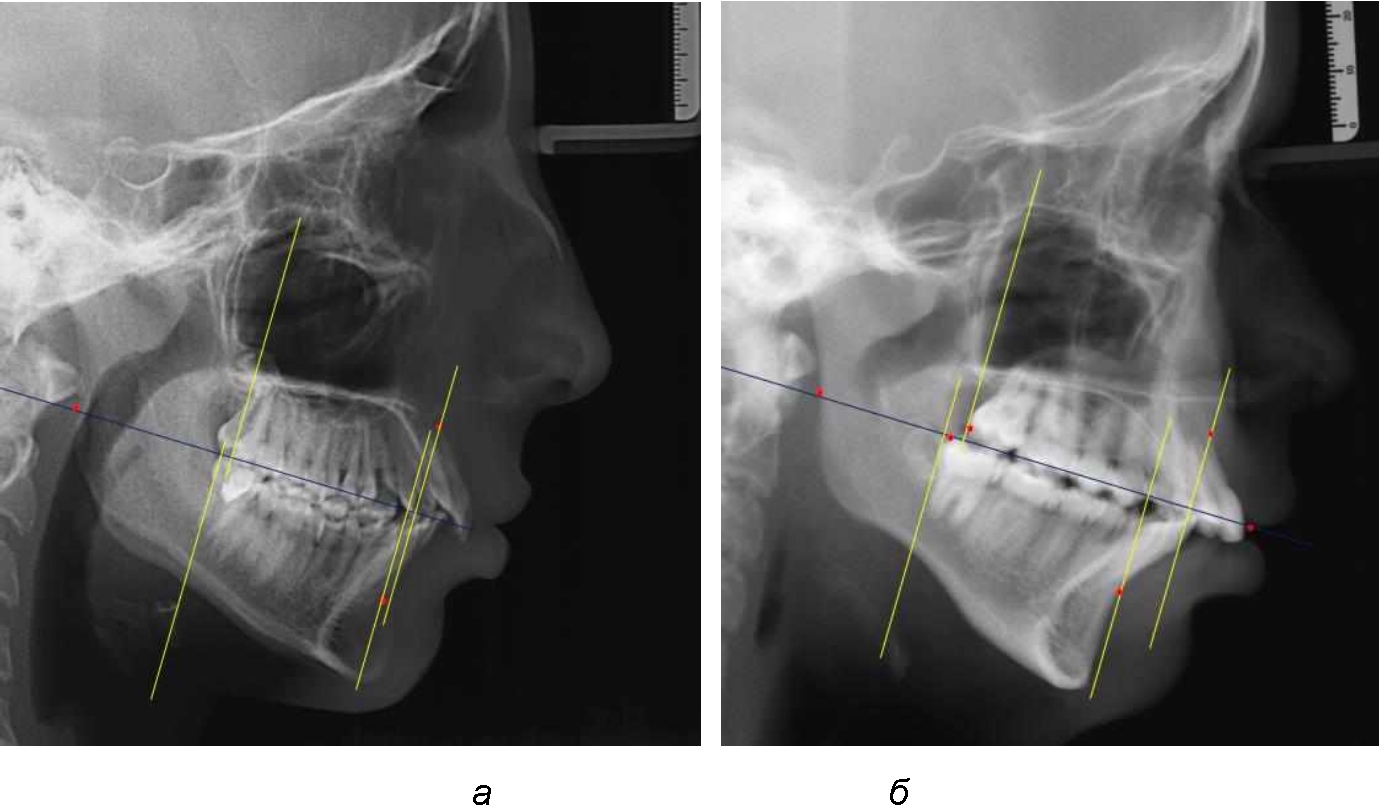

Аналогичное расстояние было отмечено и при расположении дистальных окклюзионных точек верхней и нижней челюсти (рис. 2).

Рис. 2. Положение апикальных точек и челюстей при нормопозиции (а), антепозиции (б) и ретропозиции (в) верхней челюсти

При всех вариантах положения верхней челюсти, было отмечено, что альвеолярно-денталь-ные размеры верхних зубо-челюстных дуг были близки по значению к аналогичным размерам нижней челюсти и разница в размерах не превышала 1,0–1,5 мм, а средняя величина различия показателей составляла (1,07 ± 0,54) мм.

Расстояние от конструируемой точки окклюзионной плоскости на ветви челюсти («rmРOcP») до апикальных точек Downs на обеих челюстях также коррелировало между собой, и средняя величина различия показателей составляла (1,23 ± 0,69) мм. Проекция нижней апикальной точки на окклюзионную линию, как правило, располагалась несколько кпереди проекции верхней апикальной точки, на величину около 1 мм, что соответствовало оптимальным данным Wits-анализа.